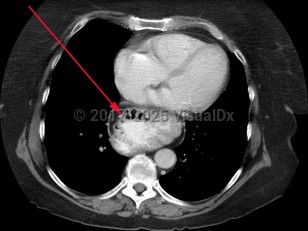

diflucortolone, 50-59 year old Female

231 Diagnoses match 0 of 1 findings